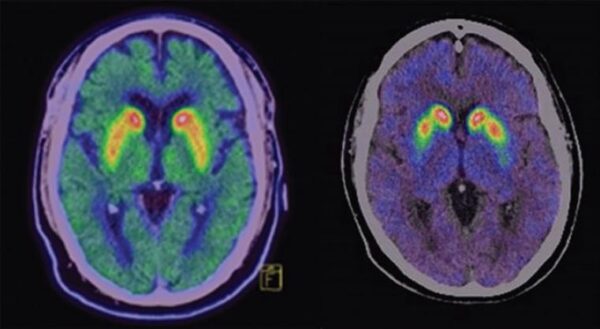

La tomografía por emisión de positrones constituye una modalidad de imagen molecular de alta sensibilidad que permite visualizar procesos fisiológicos y bioquímicos en seres vivos mediante la detección simultánea de…